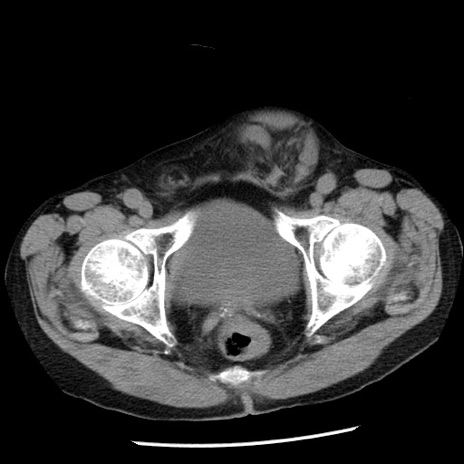

症例26(横断像)

【症例】80歳代男性

【主訴】嘔吐

【現病歴】昨晩2回嘔吐あり、今朝になっても嘔吐あり。来院。

【既往歴】胃潰瘍

【身体所見】意識清明、BT 37.6℃、BP 166/95mmHg、HR 100bpm、SpO2 97%、腹部:平坦・軟、腸蠕動音聴取良好、圧痛なし。

【データ】WBC 21900、CRP 1.46